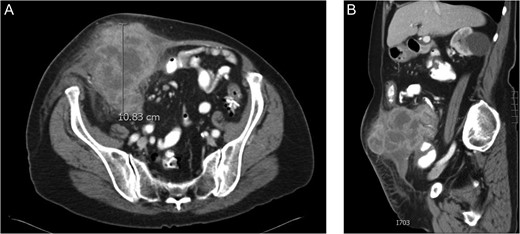

CT scan showed a mass arising from the right colon eroding through the abdominal wall almost to the level of skin (Fig. 2A and B). Of note, the scan showed no evidence of distant metastases. The patient was referred for surgical evaluation and desired definitive treatment. The patient was not a candidate for full length colonoscopy secondary to severe diverticular disease and segmental stenosis.

(A) CT scan of the abdomen in cross section revealing a large right sided colon cancer eroding through the rectus sheath almost to the level of the skin. As seen in the image, the patient was not obstructed at the time of presentation. (B) CT scan showing the mass from a sagittal perspective. The liver had no evidence of metastasis.